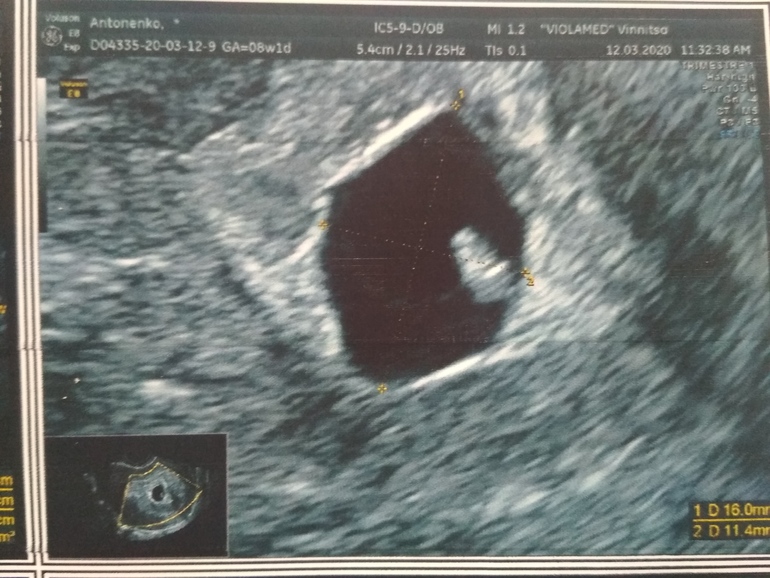

Подтверждение ЗБ